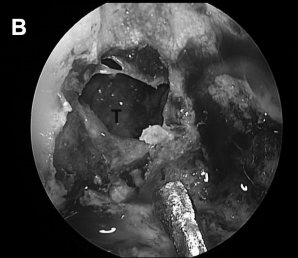

▼进行斜坡凹陷处(CD)和海绵窦内壁骨质磨除,暴露肿瘤包膜的内侧边缘(B)

▼术中见胆固醇肉芽肿包膜,进行切除并送标本活检后,逐渐切除肿瘤病变(图6C)。